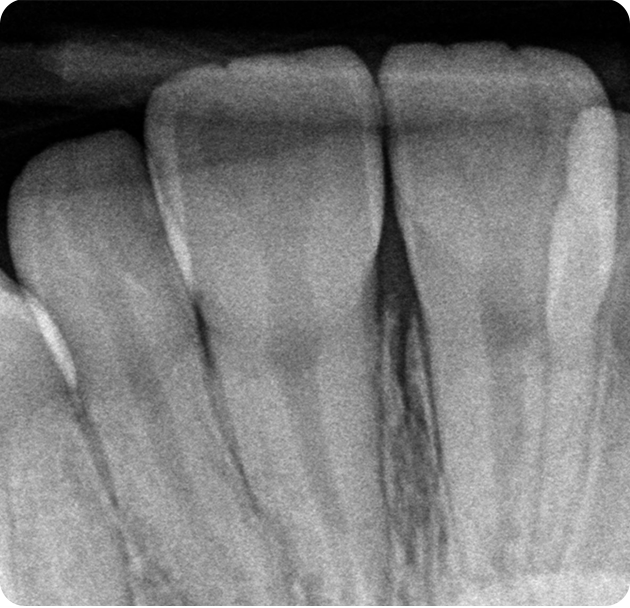

• Digital X-Rays: Get faster, safer, and clearer images with minimal radiation exposure.

Digital X-Rays

See More. Diagnose Better. Treat Smarter

Discover how our Digital X-ray technology gives your smile the advantage of clarity, safety, and speed.

At Smile Invent, we use Digital X-rays not just for images — but for insights. Whether it’s early decay, bone structure, or alignment issues, digital X-rays help us detect problems before they become painful or expensive.

• Early detection of cavities & gum disease

• Planning implants & root canals

• Tracking bone loss or orthodontic progress

• Painless and fast process